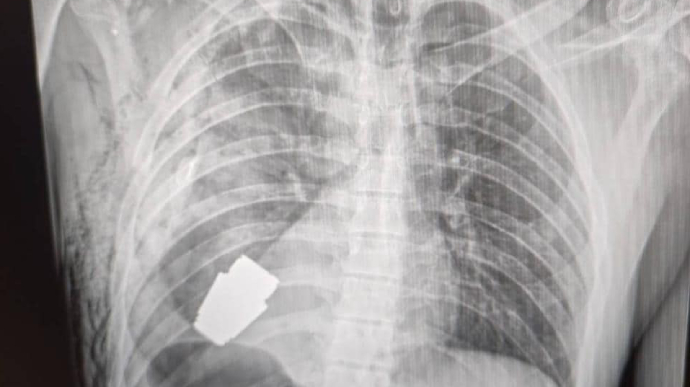

Українські лікарі під наглядом саперів провели унікальну операцію: видалили гранату ВОГ, що не розірвалася, з тіла військового.

"Не кожне поранення в області серця є смертельним! Військові лікарі провели операцію з видалення гранати ВОГ, яка не розірвалася, з тіла військовослужбовця, - пише вона. - Її було видалено у присутності двох саперів, які страхували безпеку медичного персоналу.

Операція проводилася одним з найдосвідченіших хірургів ЗСУ - Андрієм Вербою, без електрокоагуляції, оскільки граната могла детонувати у будь-який момент".